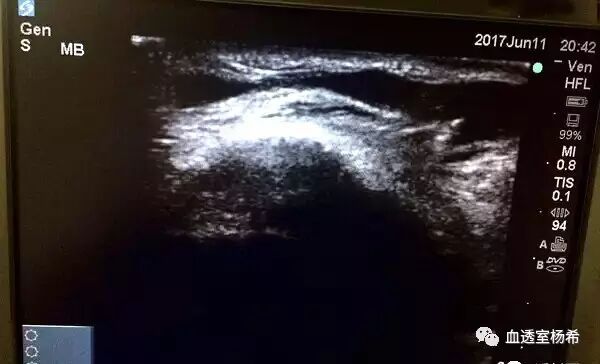

☞【多普勒超声检查及其他影像学检查】:多普勒超声是1项无创伤性检查技术,通过测定超声在不同血流速度中产生的频移计算出血流速度,而再通过血管内径测定计算血流量,是临床最为常用的血管通路评估手段。其优点在于不仅能测定血流量,同时能直接看到血管狭窄,并定量评价血管狭窄程度,也可以观察内瘘有无侧枝循环和瘘管内的附壁血栓。缺点是不同的机器有不同的流量速率计算方法,因此不同机器都有不同的误差,可能对流量的估算过高或过低,导致得出的结果存在差异。同时其准确性很大程度上会受检查者水平的制约,因此要求检查者经验丰富。

■  B 超检查显示内瘘有狭窄或闭塞;